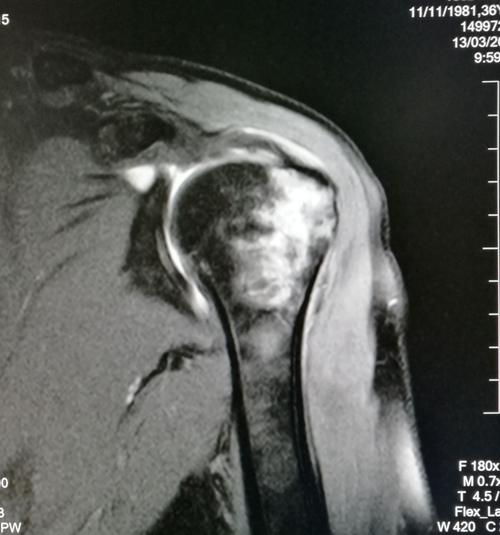

该患者行ct检查提示肩关节后脱位合并反bankart损伤 反hill-sachs

水平位ct显示肱骨头后脱位.